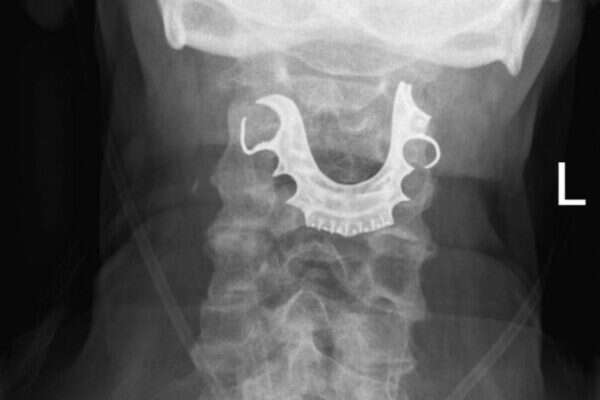

האנטיביוטיקה לא עזרה, והוא חזר לבית החולים אחרי מספר ימים לבדיקה נוספת. הרופאים הזמינו צילום רנטגן, וחשפו את הבעיה. מתקן חלקי של שיניים תותבות, שכולל לוחית ושלוש שיניים, נתקע בגרונו.

האיש חשב שהוא איבד את השיניים בבית החולים כשעבר את הניתוח, אך מסתבר שהן נשארו אצלו כל הזמן הזה. לא ברור איך הגבר בלע אותן, אך בעבר תועדו מקרים נוספים של בליעת שיניים תותבות בזמן הליכים כירורגיים בהרדמה.